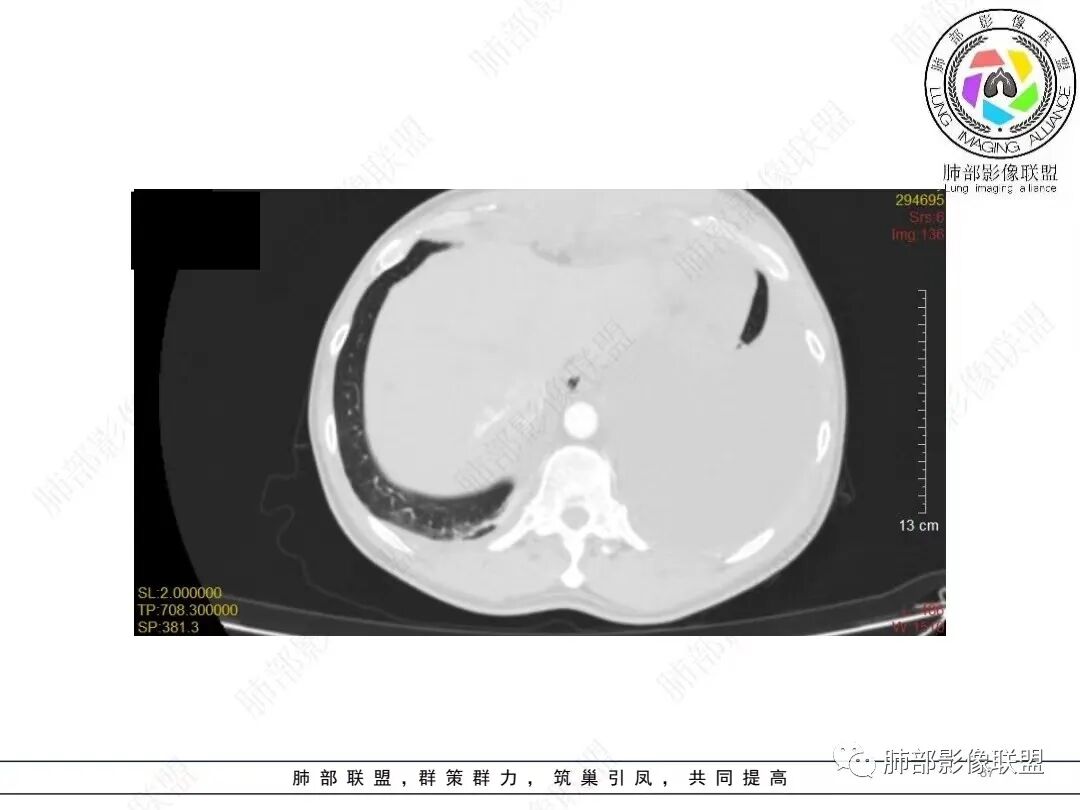

目前的图:主要是胸部的病灶。胸膜弥漫斑块状增厚。强化明显,内部血管漂浮。前纵隔部分病灶强化偏低。

2.影像学特点:病变范围相当广泛,多发块状影累及纵隔、胸膜、前胸壁(胸大肌下)、前上腹壁等。胸膜弥漫性斑状增厚为主,明显强化,纵隔旁椭圆形块影较密实,沿胸膜分布趋势,未见支气管等结构进入。后纵隔块影较大,占位效应明显,肺静脉受累狭窄。双侧胸腔积液。

肿瘤侵犯可以出现胸腔积液,静脉回流障碍也可以,如心功能不全,如本例肺静脉及左心房受压等等。